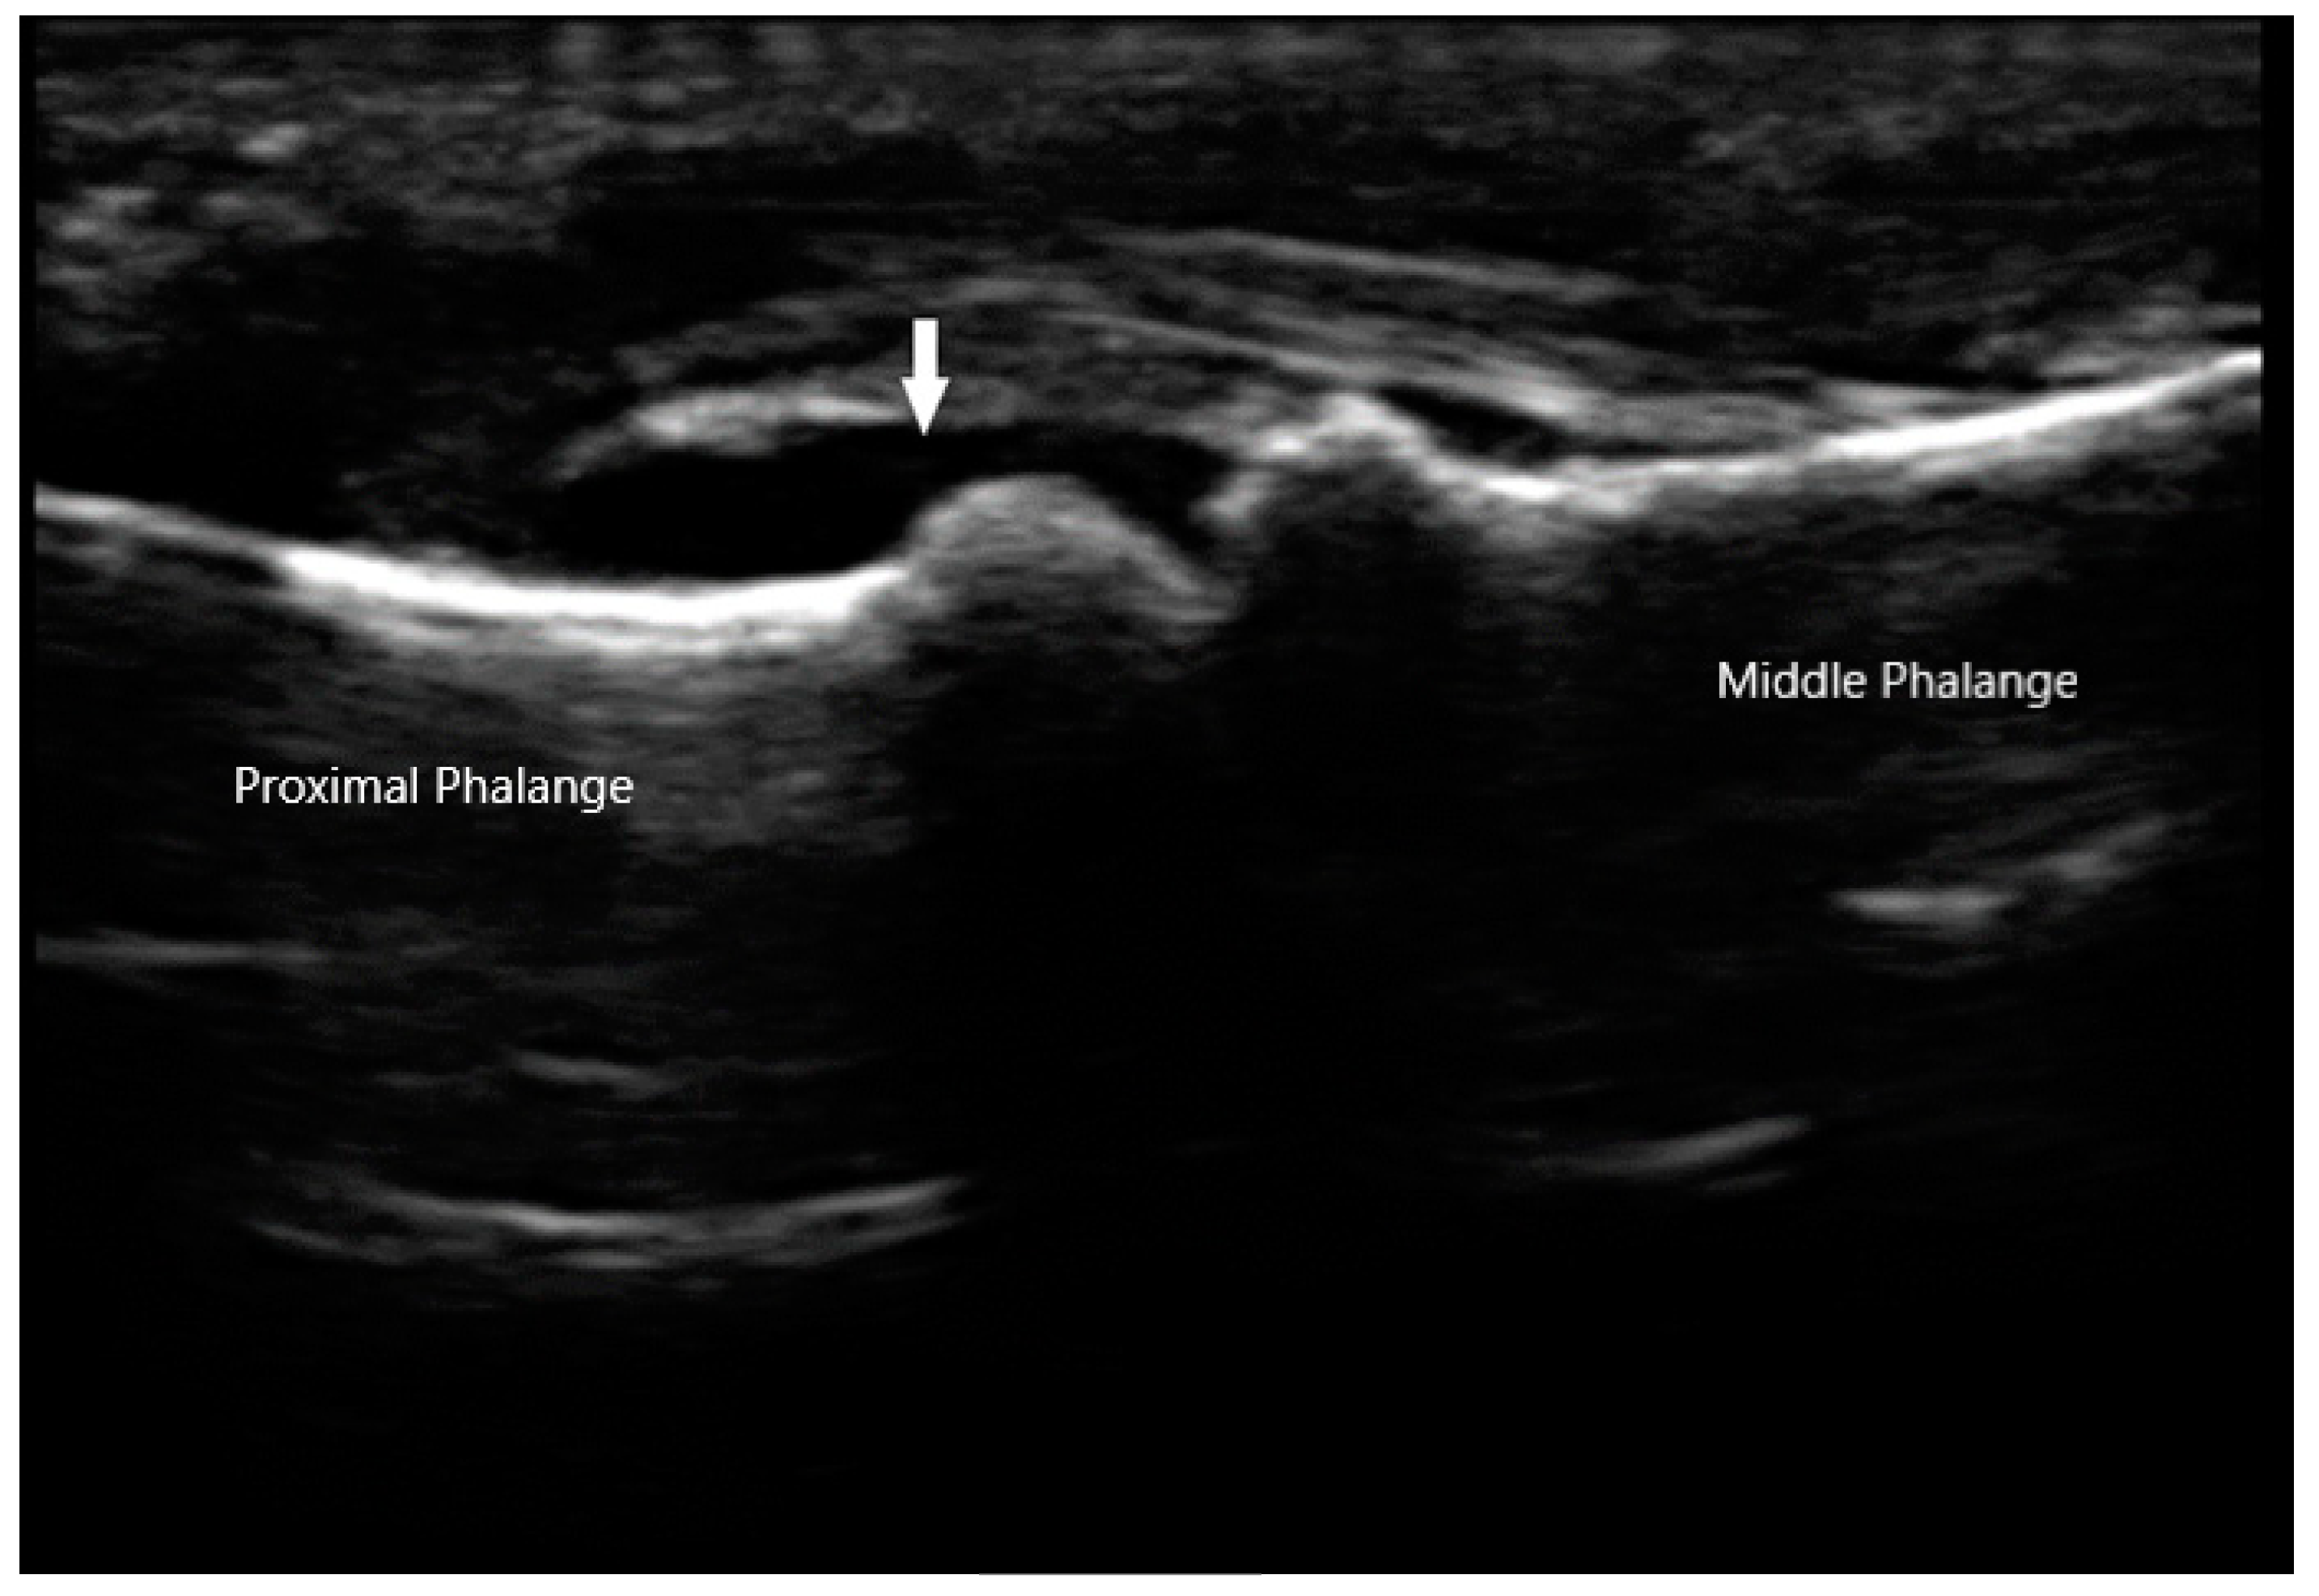

The Outcomes Measures in Rheumatology (OMERACT) group has established a consensus-based system to define and grade synovitis identified by greyscale and power Doppler [19]. Synovial hypertrophy is visualized as abnormal hypoechoic material in intra-articular tissue that is non-displaceable and non-compressible (Figure 2). In order to distinguish it from an effusion, sonographers can apply pressure on the transducer in order to evaluate for compressibility. It is graded on a scale of 0 to 3. Grade 1 is defined as minimal synovial thickening without protrusion over the adjacent bone. Grade 2 is more extensive synovial thickening with bulging over the bone. Grade 3 describes extensive thickening with extension beyond the joint. Angiogenesis is another hallmark of synovitis, and this hypervascularity can often be detected by increased power Doppler signal, which can also be graded from 0 to 3 [20]. Grade 0 refers to lack of Doppler activity. Grade 1 is mild activity. Grade 2 and 3 are defined as Doppler signals covering <50% and >50% of the joint area respectively. Tenosynovitis is characterized by hypoechoic material or fluid within tendon sheath (Figure 3).

Figure 2. Synovial effusion (arrow) of proximal interphalangeal joint.